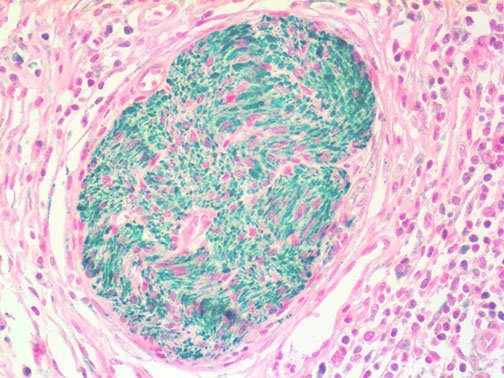

This activation induces inflammatory monocytes to highly express IL-6, starting a localized and then systemic cascade effect that results in hyperproduction of IL-6, which accelerates the inflammatory process. Because IL-6 also increases vascular permeability, excessive levels cause blood vessels to become very leaky. This, along with clotting factors released from vascular endothelial cells, stimulates the coagulation cascade, resulting in microthrombosis (tiny clots), which leads to ischemia and tissue death of the kidney, intestines, heart, liver, brain and extremities.